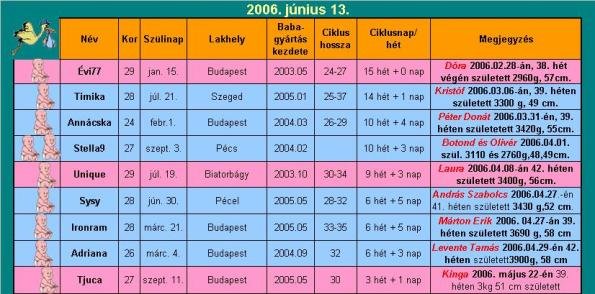

Mi jól vagyunk, Laura egyre nagyobb, már átalussza az éjtszakát (8-10 óra egyhuzamban). Igaz, hogy éjjel ½ 12 előtt nem tudja elkezdeni az elelvást, de azért legalább ez is valami…

Szopizik ezerrel, szépen nő a súlya. Már visszamosolyog ránk, imádnivaló! És tudunk vele beszélgetni, olyan szóf@sása van néha, hogy az csak na…

Nem semmi, 2 hetesen ekkora utat megtenni Kingával! .)

Pelus: a Libero newborn szerintem szupi, a 3-6 kilós is jó (mini) , de 4,8 kg-nál már kicsi. Illetve szerintem nem készültek fel a palus gyártók arra, hogy egy 2 hónapos gyerek alszik 10 órát egyhuzamban, mint Laura.